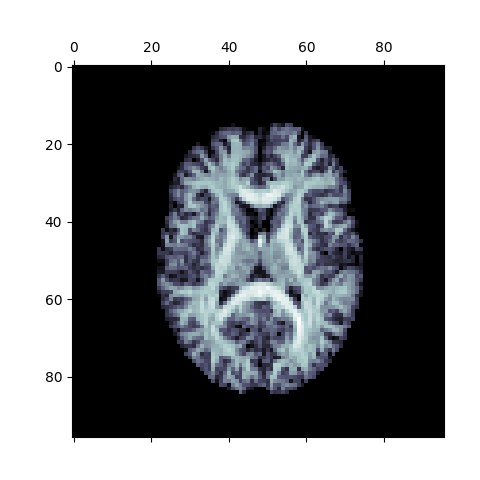

plt.matshow(np.rot90(ap[:, :, 10]), cmap=plt.cm.bone)

plt.savefig("anisotropic_power_map.png")

Anisotropic Power Map (Axial Slice)

The above figure is a visualization of the axial slice of the Anisotropic Power Map. It can be treated as a pseudo-T1 for classification purposes using the Hidden Markov Random Fields (HMRF) classifier, if the T1 image is not available.